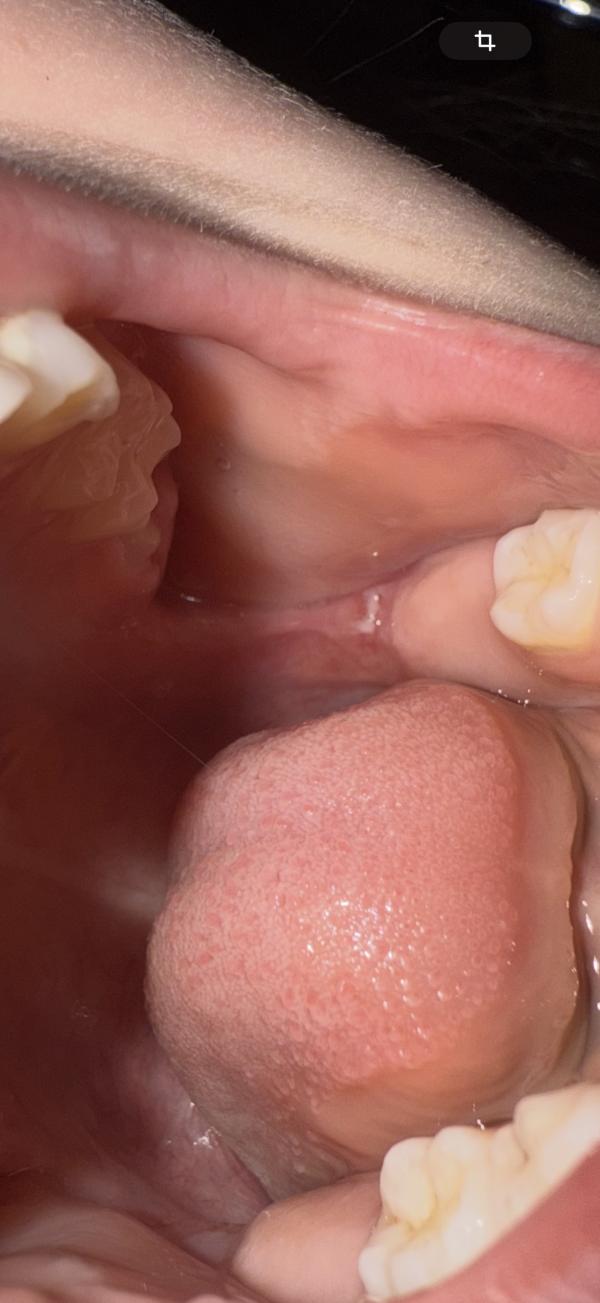

Что это во рту у ребенка после травмы: гной или нет?

post image 2

Девочки ,что это может быть зубами ,дочка острым предметом пихнула ,была кровь 🩸 сейчас вот такое ,но я не думаю что это гной за один день образовался

Во рту раны так рубцуются. На месте удалённых зубов тоже белое обычно

Просто повреждение слизистой. Пройдёт